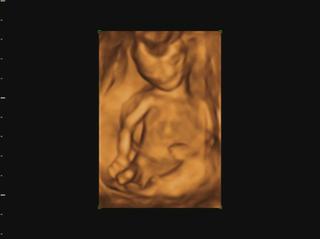

už som objednaná aj na 3D do KE... konečne môžem kľudne spávať 😀 😀 😀

@veronika1417 medzi 3d a 4d nie je skoro žiadny rozdiel, takže všade kde robia 3d robia aj 4d, lebo to štvrte D znamena čas,4d-real time, že mimi vidiš v realnom čase ako sa hybe.čiže stale je to 3d-trojdimenzionalne videnie babatka v 4d-realnom čase 😉

@luci66 juuuj Ty mas ake super informacie 🙂 to som vobec nevedela ze sa meria nosova kosticka a sijove prejasnenie, ten doktor na sone je taky dilino cely cas je ticho len tam znudene sedi a mna ide slaktrafit a trpnem ci je vsetko v poriadku ☹ ja som si veru sono uzila velakrat lebo sme dost lezali v nemocnici ale uz je to oki. Teraz uvidim miminko az 30.6 co je strasne daleko ☹ to uz budeme v 20 tyzdni 🙂 takze aj obrazok by mal byt uz kraaasny 🙂 mozno si dam aj ten 3D viem ze v Ba robia aj 4D ale v NR len 3D